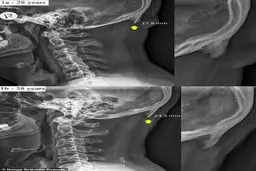

تغییر شکل جمجمه به دلیل کار زیاد با موبایل + عکس